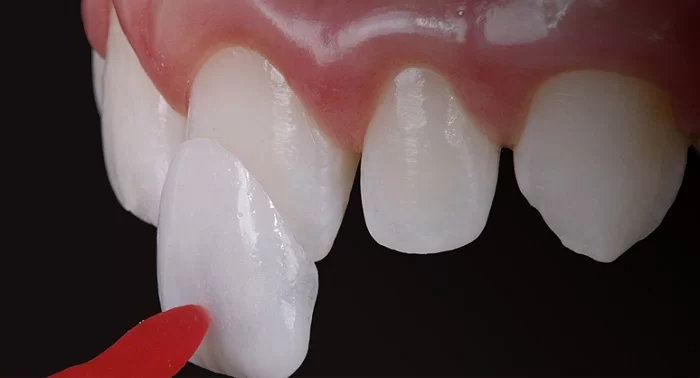

Dán răng sứ

Phương pháp dán sứ cho răng bị mẻ là một kỹ thuật che phủ, bọc lớp mặt dán với độ dày thường từ 0.2 mm – 0.5 mm để che phủ vết mẻ trên răng cửa. Tùy thuộc vào vị trí và mức độ mẻ, mặt dán có thể được sử dụng để che phủ một phần hoặc toàn bộ mặt trước của răng.

So với việc bọc răng sứ, kỹ thuật dán mặt sứ cũng qua các bước tương tự. Tuy nhiên, thay vì mài nhiều, bác sĩ chỉ loại bỏ một phần lớp men răng bên ngoài, giúp thủ tục trở nên đơn giản hơn.

Phương pháp này mang lại vẻ đẹp tự nhiên cho hàm răng và gương mặt, nhờ màu sắc của sứ tương tự như răng thật, khiến người đối diện khó có thể phát hiện. Đồng thời, đây cũng là phương án để khôi phục sự toàn vẹn ban đầu cho răng của bạn. Thời gian thực hiện nhanh chóng và hiệu quả lâu dài là điểm mạnh khiến nhiều người ưa chuộng phương pháp này.